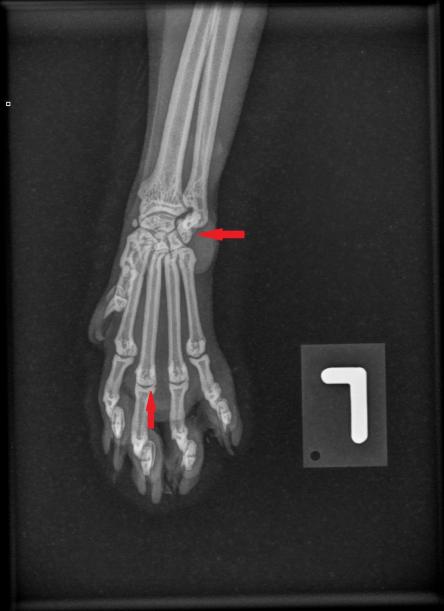

Die Besitzerin berichtet, dass der Kater recht lahmheitsfrei laufe, aber nicht über eine grosse Sprungkraft verfüge. Die Beine von Maxwell sind eher kurz und er scheint hinten und vorne X-beinig. Der Gang der Katze wirkt staksig; eine eigentliche Lahmheit ist nicht zu sehen. Um Aufschluss über die Situation in den Gelenken zu erhalten, werden die Vorderpfoten/Handgelenke, Hinterpfoten/Fusswurzelgelenke und die Wirbelsäule geröntgt. Es ist zu erkennen, dass Hand- und Fusswurzelgelenke gegenüber der Normalsituation eine X-beinigkeit (Valgisierung) aufweisen, an verschiedenen Stellen Anzeichen einer Arthrose vorhanden sind und insbesondere die Mittelhand- und Mittelfussknochen kurz und gedrungen erscheinen. Ein Teil der Fusswurzelknochen von Maxwell sind ausserdem zu einem einzigen Knochen verwachsen.